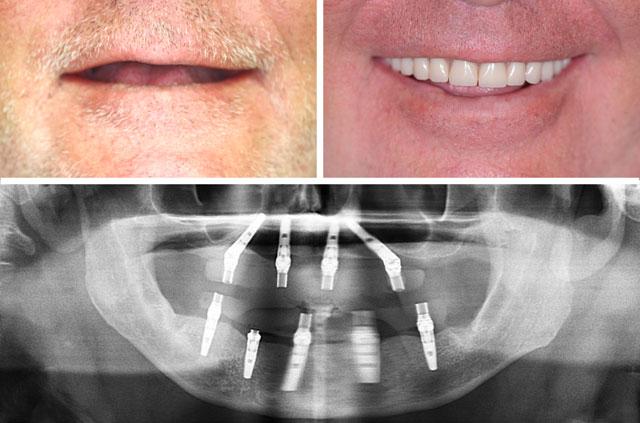

Immediate Implants and Teeth All-On-4

Patient with no teeth who could not wear dentures. 4 implants placed in anterior jaw regions with dense bone.

- •All-on-4 dental implants

- •Sinus lift for both jaws

- •4 implants in anterior jaw regions

- •Temporary dentures placed same day